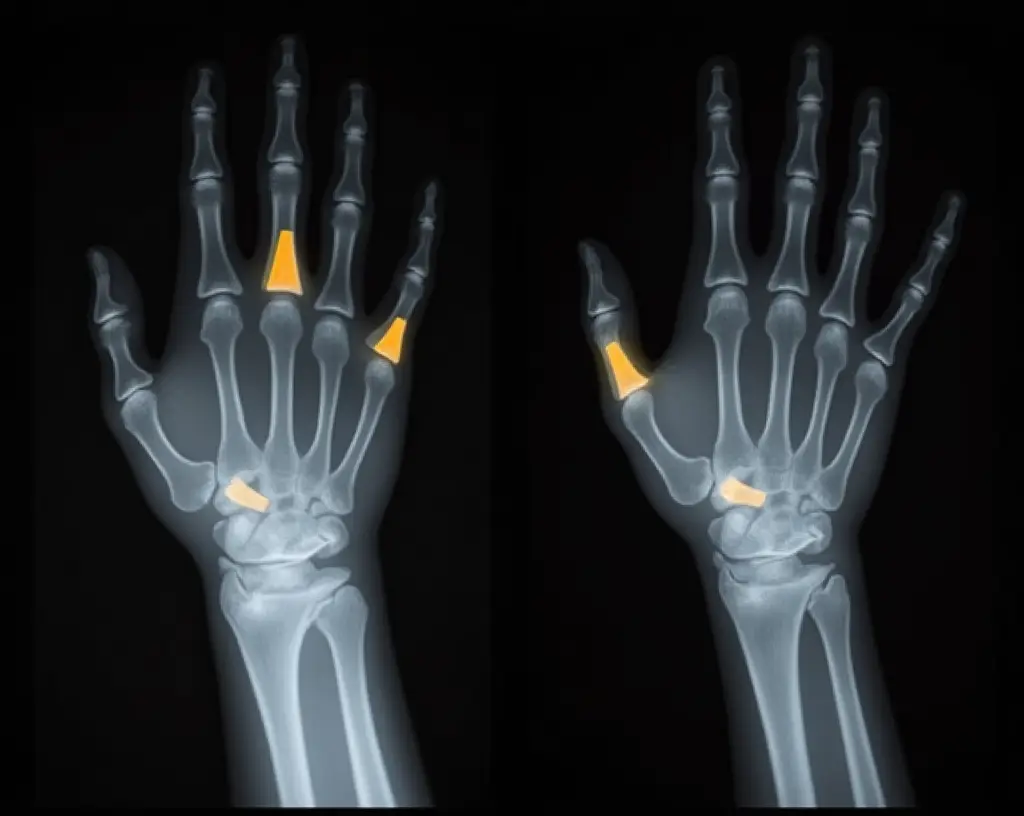

X-rays are the first and most commonly used diagnostic tool. They offer a detailed view of the bone structure and can show whether the fractured ends have been driven into each other, a hallmark of an impacted fracture. In children, buckle fractures can also be identified on an X-ray, typically presenting as a bulge or buckling of the bone’s surface without a complete break. These are especially common in the distal radius following a fall onto an outstretched hand.

In more complex or unclear cases, healthcare providers may order a CT scan to assess the depth, alignment, and involvement of surrounding joints. For injuries suspected to involve soft tissue damage, such as ligaments, tendons, or muscles, an MRI may be necessary. These advanced imaging techniques help determine whether the fracture is stable and whether surgical intervention might be required.